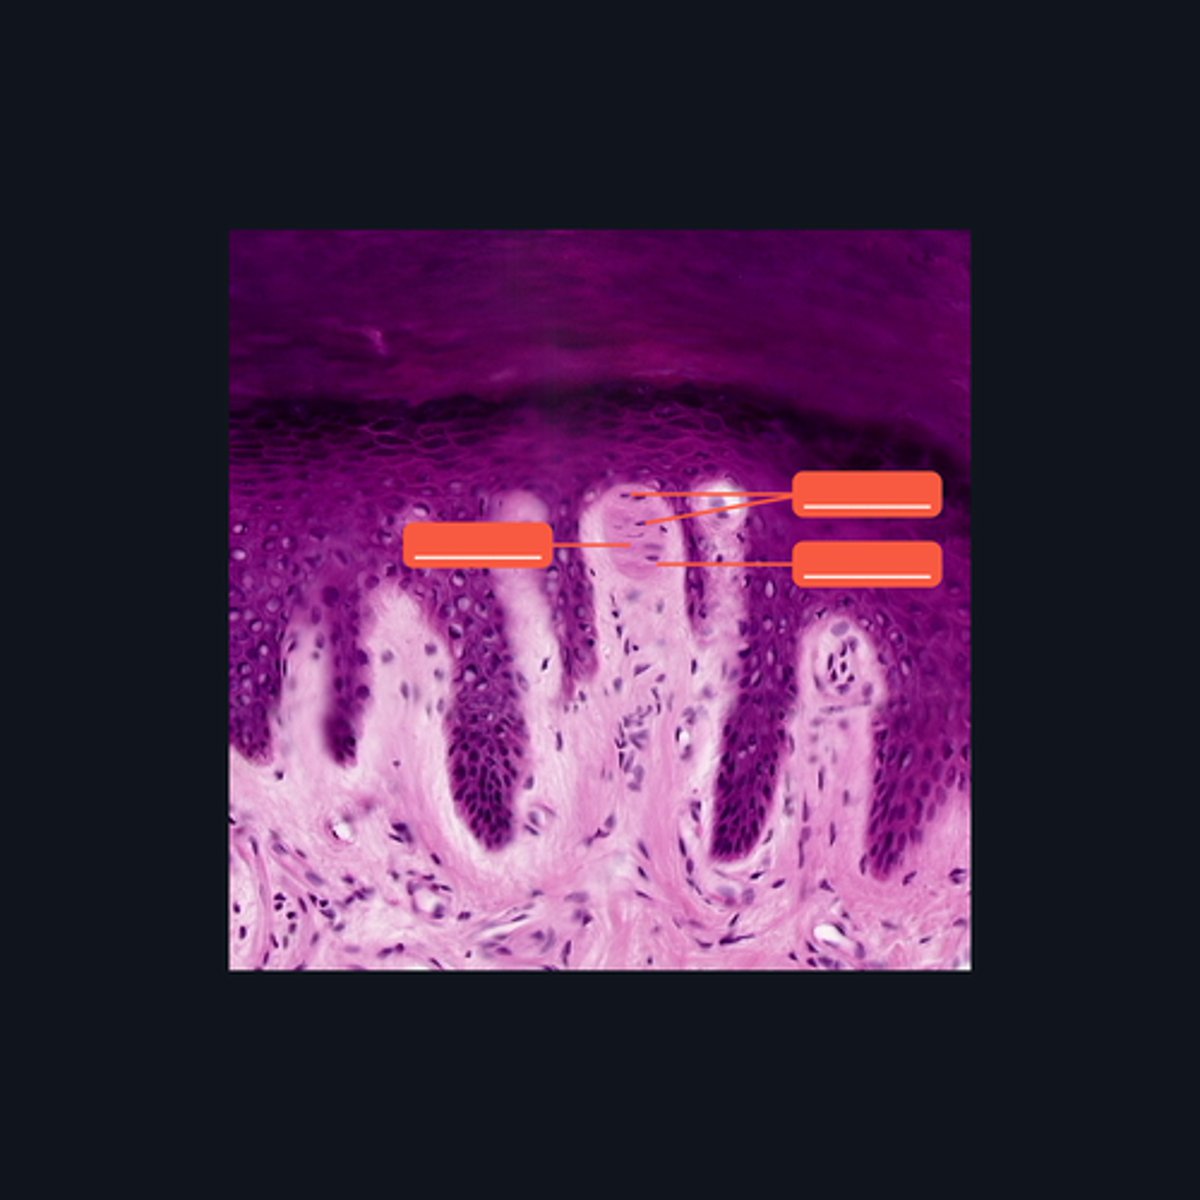

Meissner's corpuscle, Lamellar cells, and Capsule

Identify each pointed structures.